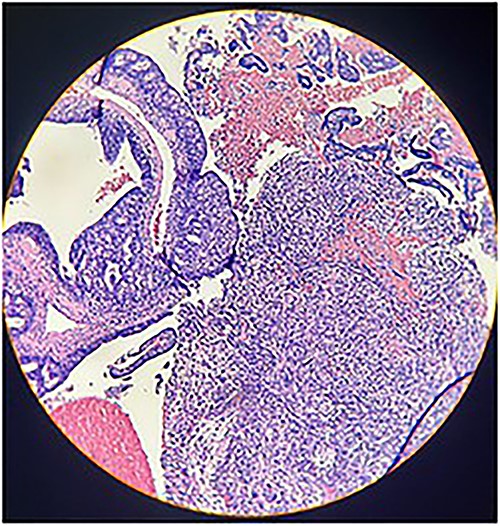

Macroscopically, an amorphous uterus weighing 397 g and measuring 12 × 9 × 7.5 cm with a brown serosa, and multinodular violaceous areas was examined. When incised, the endometrial cavity was occupied by a whitish polypoid mass of 8 × 5 cm which invaded the myometrium. In addition, multiple firm whitish nodules ~2 × 1.5 cm in diameter were identified. Bilateral ovaries and fallopian tubes appeared to be of normal morphology and size. Histologically, there was evidence of epithelial and sarcomatous components (Figs 1 and 2), and the epithelial component developed atypical glands (Fig. 3). The diagnosis of MMMT was given due to histologic findings.

Photomicrograph shows homologous sarcomatous components, composed of sarcomatous spindle shaped cells, with elongated nuclei and irregular nuclear membrane. (H&E stain ×10).

Photomicrograph shows epithelial components that form atypical glands and solid nodules with a sarcomatous component (H & E stain ×10).